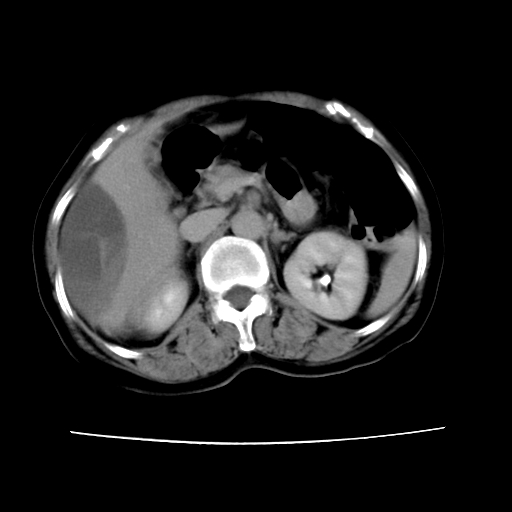

2008-6-10ct平扫

ct增强

6月份ct片显示肝内巨大混杂密度团块,伴包膜下积液(内含液液平面),增强多无明显强化。只能考虑肝占位病变,并肝内、血膜下血肿。肝ca并出血多见,而肝血管瘤并破裂出血少见。

6月份ct片显示肝内巨大混杂密度团块,伴包膜下积液(内含液液平面),增强多无明显强化。只能考虑肝占位病变,并肝内、包膜下血肿。肝ca并出血多见,而肝血管瘤并破裂出血少见。